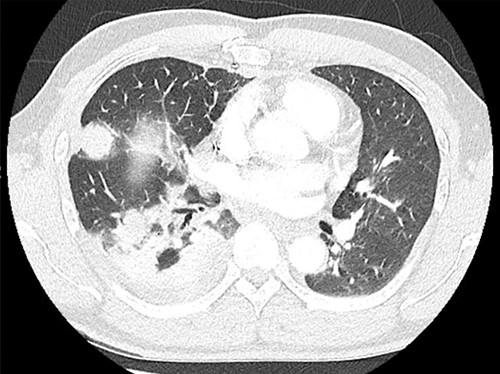

After redeveloping the symptoms of dysautonomia, he was found to have a positive anti-CASPR2 antibody level as well as recurrent disease in the right lung parenchyma and pleura (Fig. 1). His case was evaluated by a multidisciplinary team of thoracic surgery, neurology, medicine and oncology who recommended prednisone for symptom control and palliative salvage surgical resection of disease. He then underwent an uncomplicated right extrapleural pneumonectomy with diaphragm resection and reconstruction with an unremarkable postoperative course (Fig. 2). Final pathology revealed multiple foci of metastatic thymoma as well as a small focus of squamous cell carcinoma.